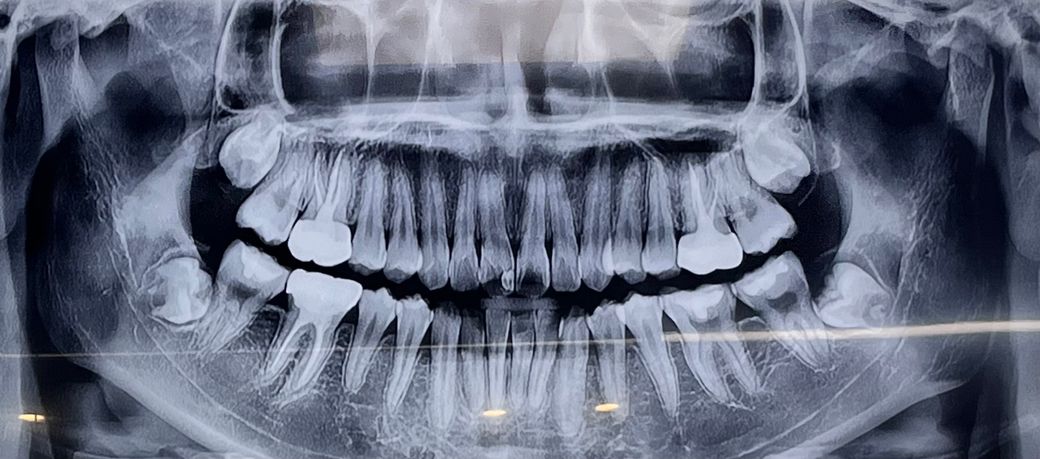

치과 파노라마 사진 보고 큰 충치 있는지 알고 싶습니다

양쪽 아래 어금니 사이 작은 인접면 충치가 있다는 건 들었어요

혹시 그 이외에 접합부 충치, 신경치료 해야할 충치 등 큰 충치가 있는지 알고 싶어요

특히 앞니, 그리고 양쪽 어금니요

위 앞니의경우는 예전에 치료를 받으신 부위인데 치아 상태에 따라서 신경치료를 하셔야될수도 잇을것같습니다. 그리고 양쪽 아래 어금니도 사이에도 충치가 있긴있습니다.

오른쪽위에 어금니의 인접면에 음영이 보이고 있습니다

그이와에므누파노라마 보다 육안으로 확인을 해야 충치여부를 정확하게 알수 있을것으로 생각 됩니다.